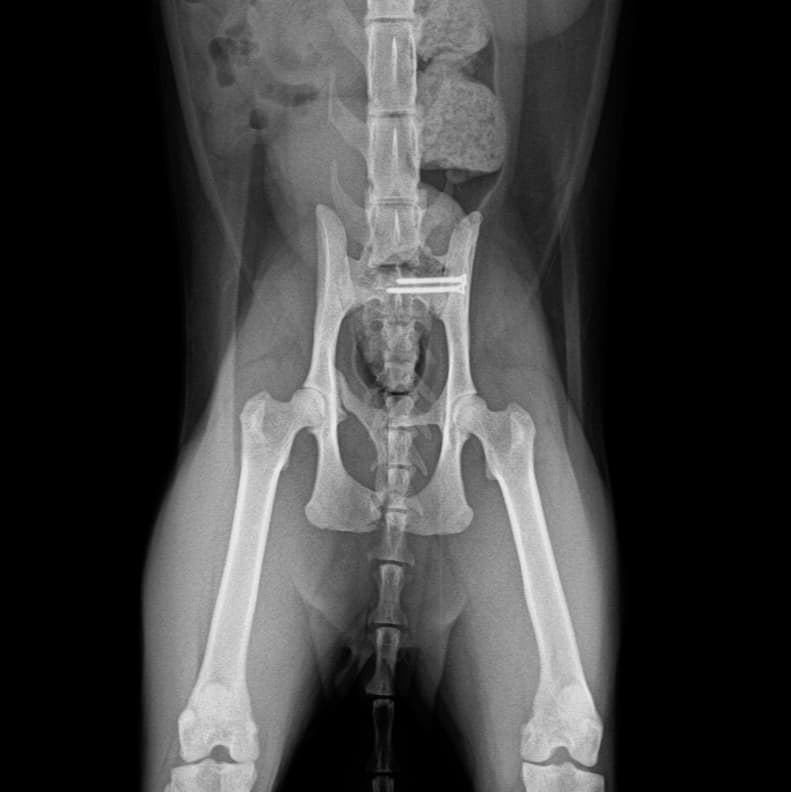

정형외과 전공의 수의사가 직접 수술합니다.

0164 채널 CT 촬영을 통해서 신속하게 고화질 영상을 얻어, 종양 유래 확인 및 전이 평가, 간문맥단락증(PSS), 선천적 뼈 기형과 같은 심화된 진단을 할 수 있습니다.

02C-arm을 통해서 좀 더 섬세한 정형외과 수술을 진행하고, 본원에서는 외과적 침습을 최소화 하는 중재적 시술 (기관 협착, 동맥관개존증(PDA), SUB 등)을 진행하고 있습니다.

13수술 중 골절 상태 혹은 이식물 적용 후 상태 등 육안으로 명확히 확인하기 힘든 상태를 X-ray 확인하여 정확한 수술 결과를 만들어 내는 것이 가능